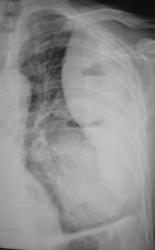

Иллюстрации 3, 4. Справа определяется почти диффузное усиление, обогащение и деформация легочного рисунка, на фоне чего дифференцируются очаговоподобные тени, округлые мелкие просветления. Тень правого корня полностью нивелирована, смещенным вправо средостением.